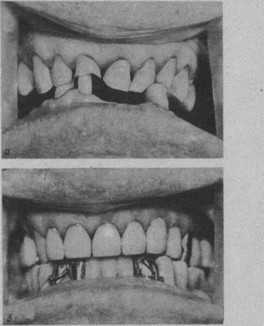

Рис. 23. Устранение нарушений окклюзии при деформации зубных рядов с патологической стираемостью с понижением межальвеолярной высоты и нижней трети лица.

Окклюзионная поверхность на верхней челюсти выровнена литыми комбинированными коронками, 3 213 покрыты коронками. Больной протезирован съемным протезом. а — до протезирования. Видна деформация окклюзионной поверхности зубных рядов. Пародонт зубов,’ удерживающих межальвеолярную высоту, испытывает большую функциональную перегрузку, о чем свидетельствуют их патологическая подвижность и атрофия пародонта; б—’после протезирования с повышением, межальвеолярной высоты.